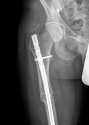

As anticipated, fixed to the femur was a 10cm surgical titanium plate of a sort used in fractures. The hope was that it would carry an identifying number. The strength of the femur means it tends to fracture only after significant trauma – a road accident, or a fall from a height. The operation is not particularly common, and in the UK such plates are routinely numbered; but in this instance there was only a simple diagram indicating the angle at which the plate was to be implanted, and the logo of the manufacturer, Treu-Dynamic, whose website states: “Treu Dynamic International (Pvt) Ltd was established in 1997 to provide quality services in the field of surgical, orthopaedic, spinal and maxillofacial instruments and implants in the Pakistan market.” While the plate is also sold into Morocco, the fact that it did not carry an identifying number means it could only legally have been implanted in Pakistan. According to Treu-Dynamic, around 500 of these plates were distributed each year in Pakistan between 2001 and 2015, meaning approximately 7,000 during the relevant period. Assuming that half of the patients were male and half of the operations involved the left leg, the number who underwent this operation is around 1,750. (These are crude figures, Coleman stresses.)

Ooh is this his actual xray?

I don't think it is because I did a reverse search and it came up with the xray on Getty images :/. Unless the dr uploaded it onto the internet at some point.

You are probably correct, had assumed it was the actual one because it might have helped with identity if the surgeon recognized their own work. imo, speculation.

That's what I thought and why I did the reverse image. It's a 30 yr old guys though :/ could have been useful :)